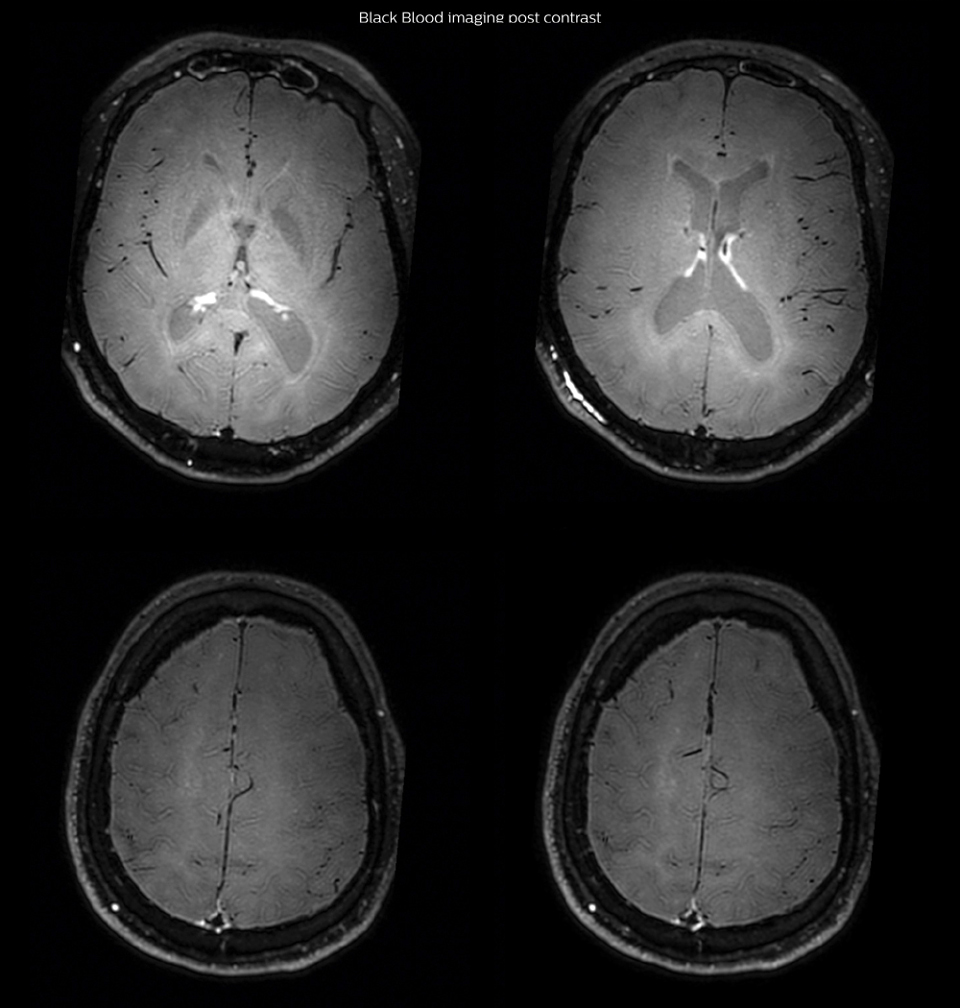

MRI examination with Black Blood imaging

After a conventional routine MR imaging examination, the suspicion of vasculitis arose, therefore we performed an MRI including Black Blood imaging in a separate session. The dedicated ExamCard includes diffusion, FLAIR, MR angiography

using TOF, and 3D T1 MRA with bolus injection. This ExamCard also includes Black Blood imaging before and after contrast. This examination was performed on our Ingenia 3.0T. Black Blood scan time 4:39 min, acquired voxel size 0.75 x 0.75 x 1.0 mm, 21 slices.

On FLAIR images we can see some nonspecific high signal abnormalities in frontal white matter bilaterally. On DWI we can see acute ischemic lesions which appear with high signal intensity. Arrows show vessel wall enhancement which appears concentric and homogeneous in different cerebral territories.

Black Blood Imaging Case 1 C Post contrast1

Arrows show vessel wall enhancement which appears concentric and homogeneous in different cerebral territories.